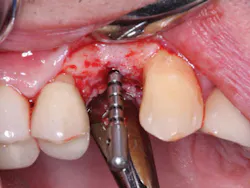

2. In the facial-lingual orientation, locate the osteotomies in the center of the ridge and parallel with the adjacent teeth. Use finger contact on the facial and lingual of the ridge while making the drill cuts. If you feel extra vibration on one or the other side of the ridge, reorient the drill appropriately (figures 4-7).

Figure 3: It is easy to center the implant osteotomy between the two adjacent teeth using your own clinical judgment and periapical radiographs.

Figures 4-7: This series of images shows a clinical situation, the cone beam images, and the freehand implant placement.